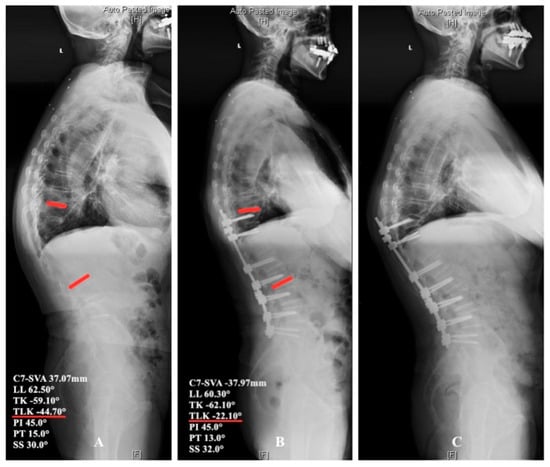

4.2. Thoracolumbar Junctional Kyphosis

4.3. Surgical Strategy